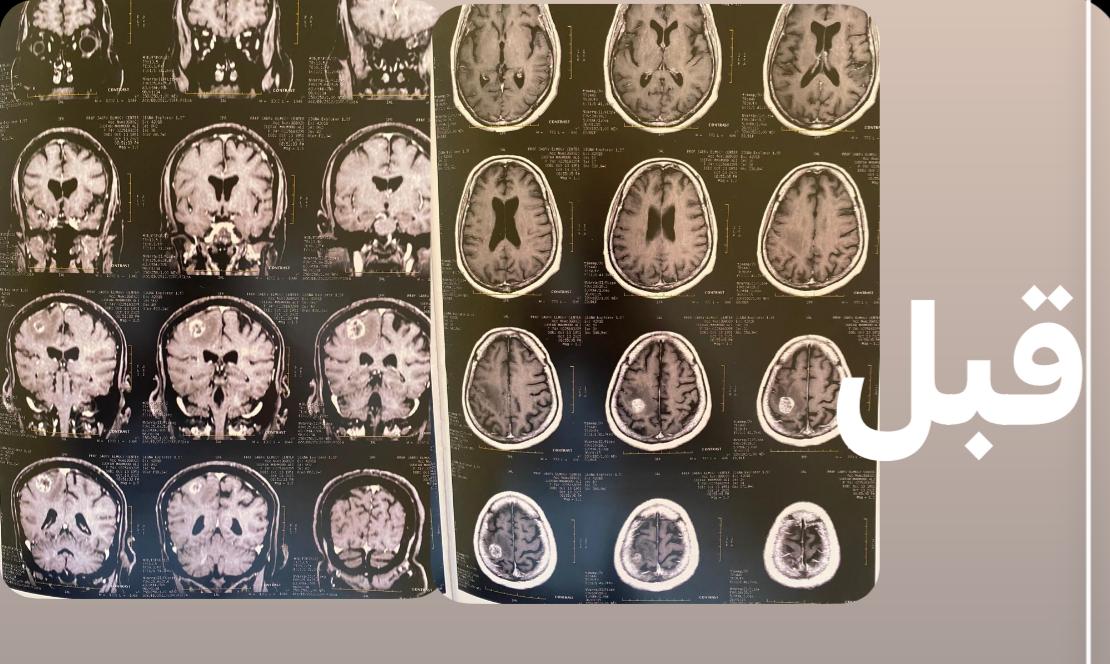

كانت المريضة قد حضرت إلى المستشفى وهي تعاني من تشنجات متكررة وتدهور في درجة الوعي وشلل تام بالجانب الأيسر من الجسم، وبعد إجراء الأشعات والفحوصات اللازمة، تبين وجود ورم بالفص الأيمن للمخ يضغط على منطقة الحركة، مما تسبب في تلك الأعراض.

وأوضح الدكتور السيد فاروق، وكيل الطب العلاجي، أن الفريق الطبي بالمستشفى نجح بفضل الله في استئصال الورم بالكامل من خلال جراحة دقيقة أجريت داخل المستشفى، مشيرًا إلى أن العملية تمت بنجاح كامل، وتحسنت حالة المريضة بعد الجراحة واستعادت وعيها الطبيعي وتوقفت التشنجات، وهي الآن تحت العلاج الدوائي والعلاج الطبيعي لحين تمام الشفاء.